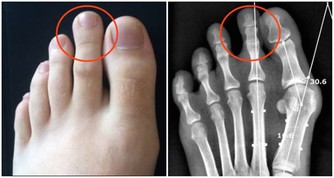

2、腳趾有「黑痣」

我們經常會在身體各個部位看到大小不同,甚至凹凸不平的黑點,這些黑點我們稱之為「黑痣」。腳趾上更是容易看到這些黑痣。那麼黑痣和癌症又有哪些聯繫呢?黑痣本身是天然無公害的,但是黑痣一旦惡化,演變成皮膚癌變將會危及我們的生命安全,即我們經常所說的癌變。

腳趾上的黑痣由於其特殊的位置就很有可能演變成為黑色素瘤。

為什麼說腳趾上的黑痣更容易演變成癌症因子呢?因為黑痣在正常情況下癌變的機率是比較小的,但是如果經常遇到摩擦、擠壓,將會增大其癌變的可能性。我們的腳趾常年處於摩擦和擠壓的狀態下,所以更加容易造成癌變。

還有一部分認為,黑痣只有在暴曬的情況下才會演變成黑色素瘤,但是我們正常情況下是不會暴曬到腳趾部位的。所以我們會容易忽略掉腳趾上的「癌症病毒」。但是,作為皮膚癌中最危險的黑色素瘤,是非常容易發展到不經常接觸陽光的部位。黑素瘤甚至可能出現在腳趾甲下面,看起來就像是一個普通的黑點。

所以如果腳趾部位出現黑痣的話,請大家要做好保護措施,經常觀察黑痣是否有異常變化,如果出現異常請儘快就醫。